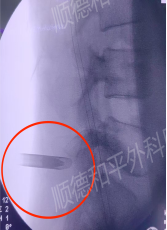

患者入院后,经过专业的问诊和摄片检查,综合判定患者可以实施“微创椎间孔镜髓核摘除术”摘除突出的椎间盘。微创椎间孔镜髓核摘除术——类似在创口插入一只铅笔大小的管子进去实施摘除处理,具有精准摘除、手术时间短、创伤小(创口仅1cm左右)、疼痛小、恢复快速等优势。

能否实施微创术取决于:患者腰椎骨骼没有钙化、年龄、工作性质、症状、个人意愿等方面综合考虑。术式:经皮椎间孔镜下L5-S1椎间盘骨墙核摘除术。